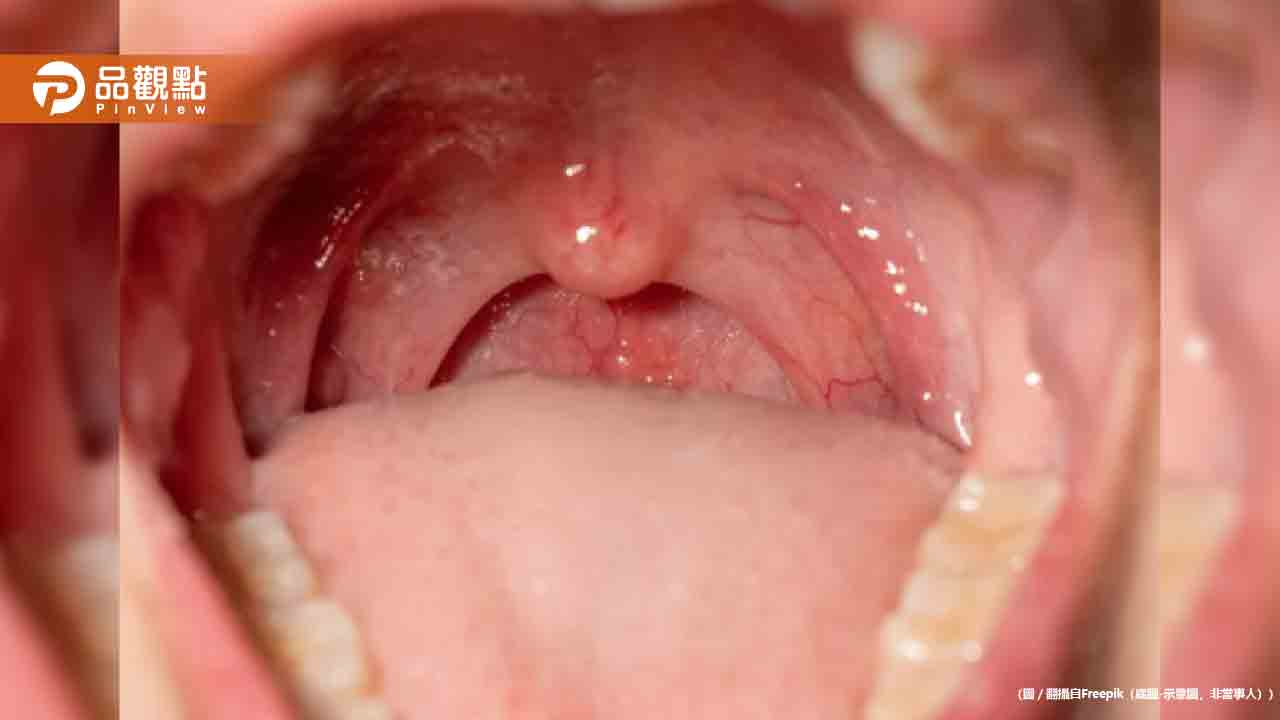

口腔癌為台灣男性惡性腫瘤發生率第四位,每年新增8000人,5年存活率不到3成。現行公費口腔癌篩檢是十大癌症中唯一採用目視進行初步判斷的癌種,且每2年進行一次,難以及時發現病灶。

該系統透過手機鏡頭拍攝各角度的口腔黏膜影像,2分鐘內即可偵測、分類和分析口腔癌及癌前病灶。診斷結果分為無燈無病灶、綠燈無風險、黃燈低風險、紅燈高風險四個等級,並給予進一步追蹤建議。綠燈者建議持續每6個月至牙醫洗牙檢查口腔,紅燈者需儘速一週內至牙醫檢查。